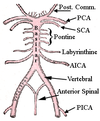

Arrangement of the arterial supply of the spinal cord

Three longitudinal vessels

Single anterior spinal artery

Paired posterior spinal artery

Composition of the anterior spinal artery

Arises in a Y shaped configuration from the two vertebral arteries at the level of the medulla and descends along the ventral suraface of the cord in the midline

Formation of the posterior spinal arteries

Arise either from the vertebral arteries or the PICA and run caudally on the posterolateral surface of the cord